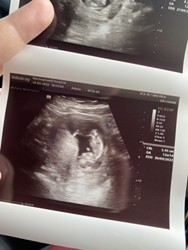

อัลตราซาวด์ มาวันนี้เลยค่ะ 08/03/2566 #12week 5day ค่ะ

ของแม่ 12week 5day ค่ะ หนูตีลังกาโชว์หมอเลย🥰